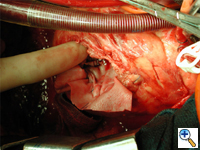

A patch of bovine pericardium is brought onto the field and first sewn to the basal and posterior septum behind the defect using 3-0 polypropylene in a continuous running fashion. Sutures must be placed far from the infarct in healthy muscle. With posterior or extensive infarcts it may be necessary to sew the patch into the mitral annulus. Sutures must be deep with a big needle. Sutures should be firmly pulled up to remove the slack but not excessively so inadvertently cutting through the muscle. A second row of sutures can augment the first. This suture line is meant to hold the patch in place rather than being water tight. This suture line is often easier to perform from the patients left side. This same suture line is continued along the inferior and and anterior walls of the septum to the ventriculotomy (Figure 5).

The patch is then sewn with full thickness sutures to the anterolateral ventricular free wall (the left side of the ventriculotomy) beyond the area of infarction, carefully avoiding the muscle (Figure 6).